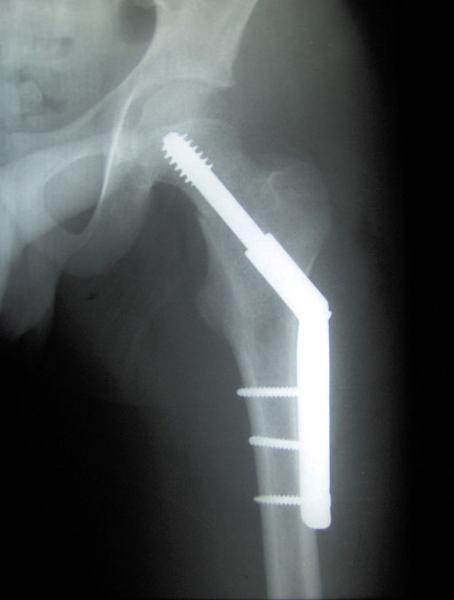

The authors performed a literature search and selected 33 trials for their analysis. Two important caveats, the population studied were adults living in the community, not in residential settings and no effort was made to identify patients with osteoporosis – a decrease in bone density due to lower amounts of calcium in bones. The primary outcome was hip fractures because they commonly lead to other health problems, but they did look for fractures at another common site, the vertebral bodies of our spine.

Why do our bones break? In general, for one of two reasons. First, and least likely, pathologic fractures – breaks in the bone due to an underlying focal disease in the bone itself, usually metastatic cancer. Vitamin D and Calcium are not prescribed and do not prevent pathologic fractures. The other, more common cause of bone fractures is trauma, and by that, I mean falling. And falling may be made worse if the bones themselves are weaker, with less calcium, when the patient has osteoporosis. That is why it is essential to understand that the two groups at greatest risk for these fractures, people who fall and people with osteoporosis were not considered. By excluding individuals living in residencies, the authors eliminated the majority of people with ambulatory problems, the ones that fall the most. At the same time, osteoporosis, the decreasing density of the bone, occurs with age and will be greater in this population. The data concerning Calcium and Vitamin D supplements are less clear for these groups.